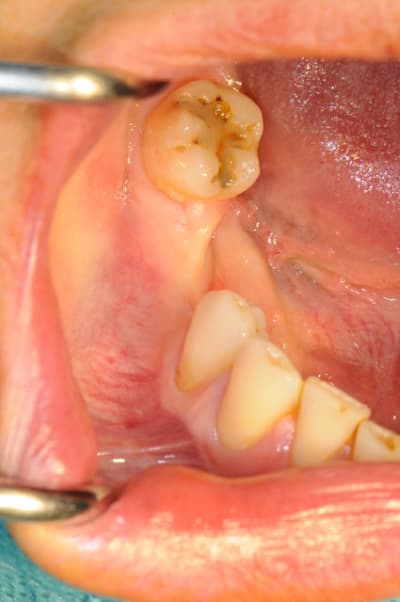

CAS 1

demande de restauration avec implant, mais, ne veut pas entendre parler de greffes et greffons.

la ROG lui semble plus "naturel".

1-2-3 situation de départ